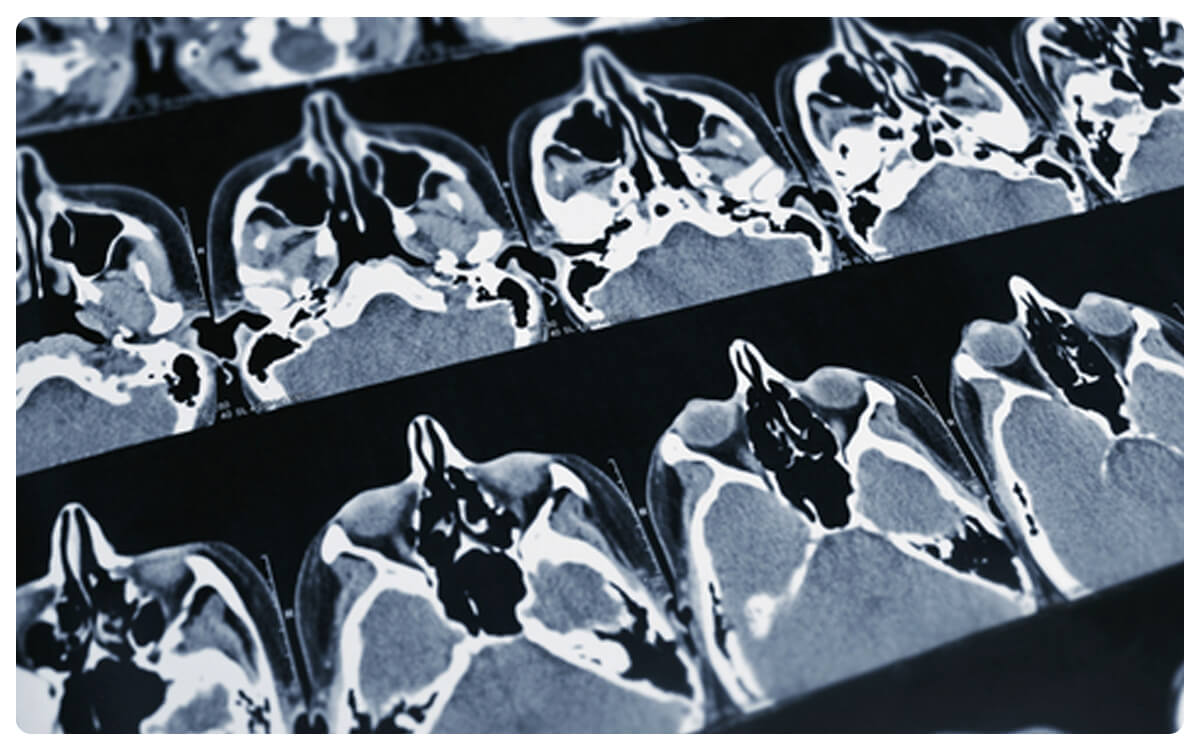

La Tomografía de Senos Paranasales Contrastada, una técnica radiologica avanzada, se posiciona como una herramienta esencial en la exploracion detallada y precisa de las cavidades nasales y los senos paranasales. A través de la tomografía computarizada y la administración de un medio de contraste intravenoso, esta técnica permite la obtención de imágenes tridimensionales de alta resolución que revelan la anatomía y posibles patologías en esta región.

La Tomografía de Senos Paranasales Contrastada desempeña un papel crucial en el diagnóstico y seguimiento de enfermedades sinusales, infecciones crónicas y otras afecciones, proporcionando información valiosa para la detección temprana de anomalías y la toma de decisiones clínicas informadas en el cuidado de la salud de los senos paranasales.